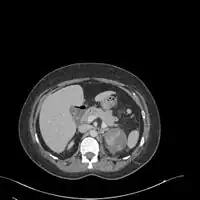

If a kidney stone is suspected (e.g. on the basis of characteristic colicky pain or the presence of a disproportionate amount of blood in the urine), a kidneys, ureters, and bladder x-ray (KUB film) may assist in identifying radioopaque stones.[9] Where available, a noncontrast helical CT scan with 5 millimeter sections is the diagnostic modality of choice in the radiographic evaluation of suspected nephrolithiasis.[17][18][19] All stones are detectable on CT scans except very rare stones composed of certain drug residues in the urine.[20] In patients with recurrent ascending urinary tract infections, it may be necessary to exclude an anatomical abnormality, such as vesicoureteral reflux or polycystic kidney disease. Investigations used in this setting include kidney ultrasonography or voiding cystourethrography.[9] CT scan or kidney ultrasonography is useful in the diagnosis of xanthogranulomatous pyelonephritis; serial imaging may be useful for differentiating this condition from kidney cancer.[10]

Xanthogranulomatous pyelonephritis is an unusual form of chronic pyelonephritis characterized by granulomatous abscess formation, severe kidney destruction, and a clinical picture that may resemble renal cell carcinoma and other inflammatory kidney parenchymal diseases. Most affected individuals present with recurrent fevers and urosepsis, anemia, and a painful kidney mass. Other common manifestations include kidney stones and loss of function of the affected kidney. Bacterial cultures of kidney tissue are almost always positive.[25] Microscopically, there are granulomas and lipid-laden macrophages (hence the term xantho-, which means yellow in ancient Greek). It is found in roughly 20% of specimens from surgically managed cases of pyelonephritis.[10]